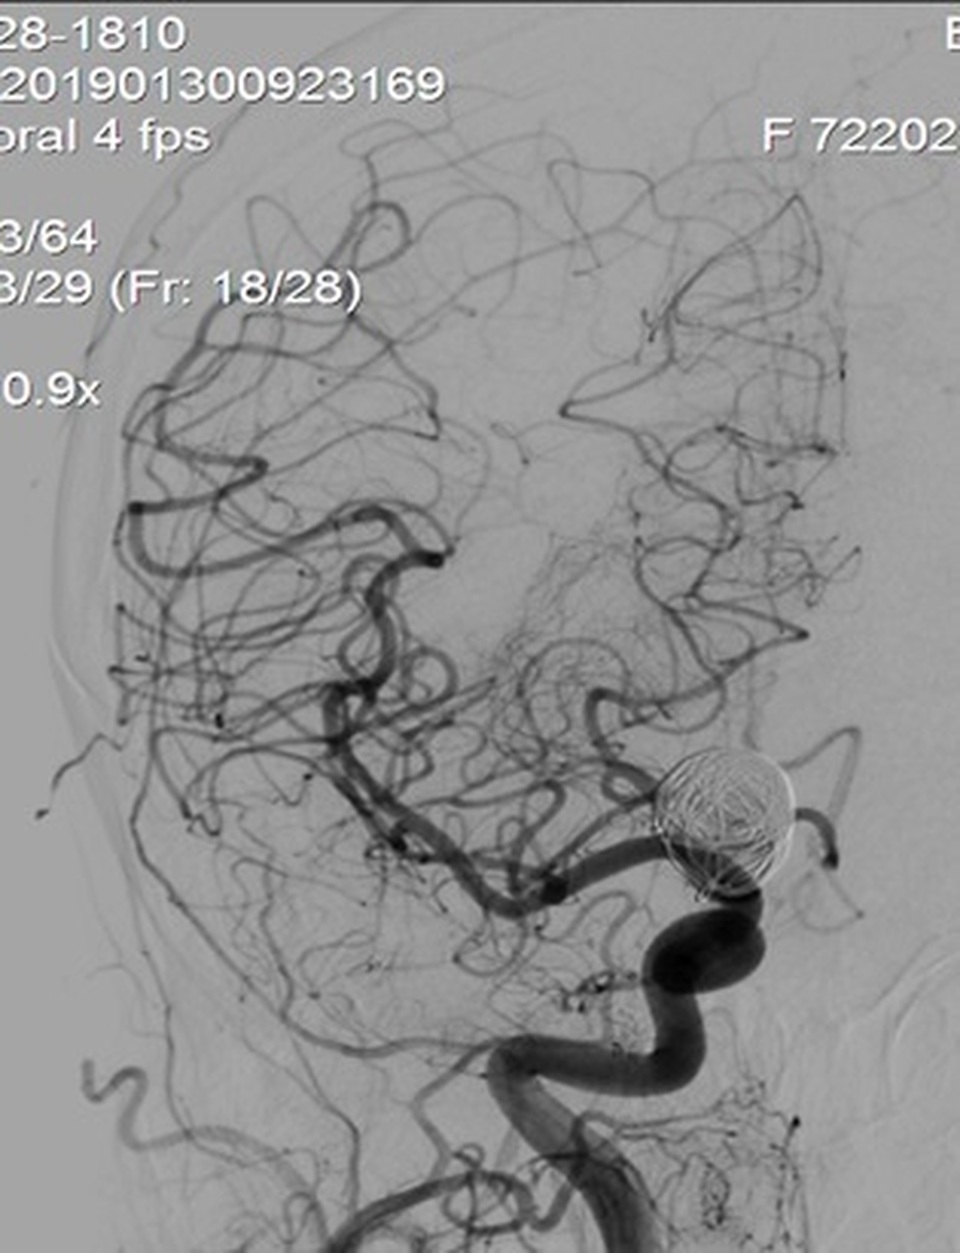

Stent chuyển dòng đặt vào động mạch cảnh trong phải phủ qua cổ túi phình khổng lồ

Nhờ quá trình can thiệp thành công, stent chuyển dòng phủ tốt cổ túi phình sau khi đã nút túi phình một phần bằng các vòng xoắn kim loại. Dòng chảy vào túi phình đã giảm đáng kể sau đặt stent chuyển hướng dòng chảy, làm giảm đến mức thấp nhất nguy cơ vỡ túi phình, cứu sống bệnh nhân.